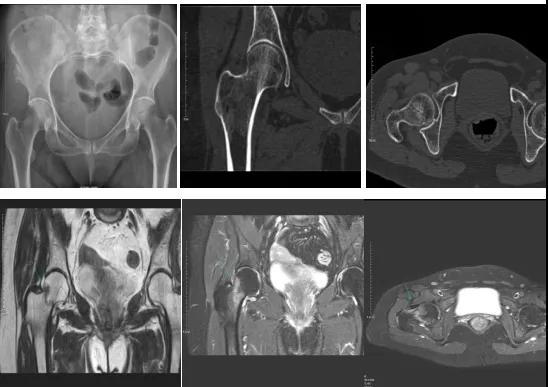

2.CT或MRI檢查。CT是斷面成像,不會(huì)出現(xiàn)重疊而導(dǎo)致漏診,同時(shí)CT還可以進(jìn)行多平面的重建,除了發(fā)現(xiàn)X線無法發(fā)現(xiàn)的骨折外,還可以三維直觀的顯示骨折的程度,對(duì)臨床治療有指導(dǎo)意義。CT無法發(fā)現(xiàn)骨裂、不全骨折或者骨挫傷,對(duì)軟組織的損傷診斷也有局限性,MRI就可以發(fā)現(xiàn)這些損傷。

DR示:右側(cè)股骨頸未見明顯骨折征象。CT右側(cè)股骨頸骨質(zhì)密度不均。患者體征明顯,為明確診斷,行MRI檢查。MRI示:右側(cè)股骨頸T1WI呈低信號(hào),脂肪抑制序列呈高信號(hào);提示右側(cè)股骨頸隱匿性骨折。